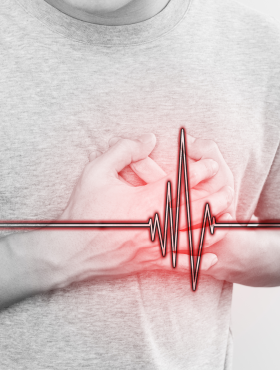

¿Fue un desmayo o algo más? Claves para entender el síncope

Autores: Md. Felipe Cañas Orduz, Cardiólogo – Electrofisiólogo A cualquiera le puede pasar: estás de pie en una fila, en…